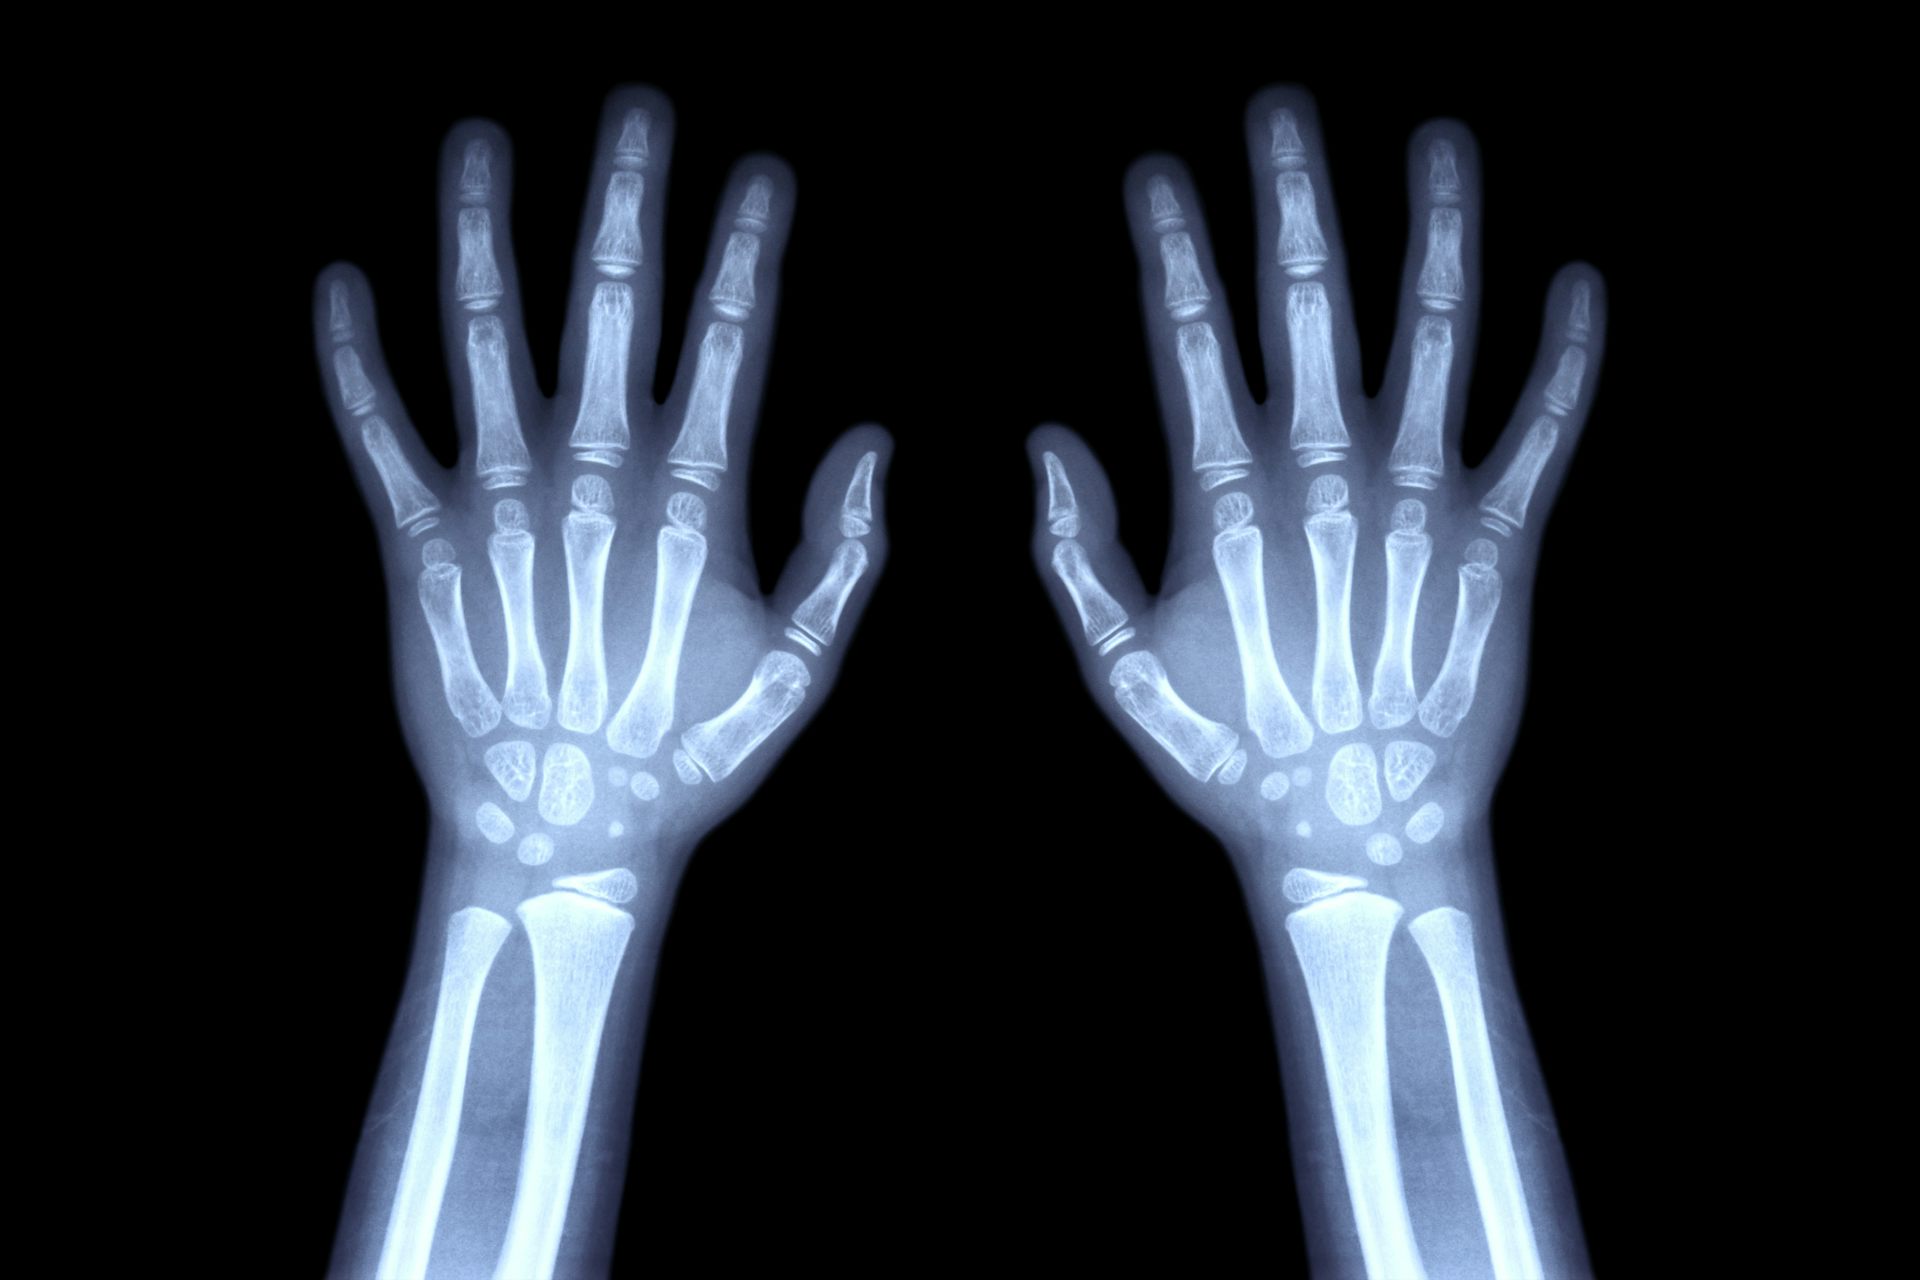

Sí. Entre los procedimientos usados para determinar la madurez de un individuo destacan, principalmente, las radiografías, que permiten estimar de manera segura la edad biológica de los niños y adolescentes analizando el aspecto de los distintos núcleos de osificación de los huesos de la mano.

Utilizando este sencillo método, los expertos pueden tanto diagnosticar y dar seguimiento a trastornos endocrinos y genéticos que afectan a la población infantil como resolver cuestiones legales y de asilo relacionadas con la inmigración de menores. Su enorme difusión entre los especialistas en Pediatría y Medicina Legal se debe, principalmente, a la insuperable relación costo-beneficio que ofrece el procedimiento en comparación con otros métodos de evaluación de la maduración esquelética del niño.

Si comparamos tres radiografías de la mano de un niño, una persona joven y un adulto, a simple vista comprobaremos que los huesos del carpo en la infancia están lejos de alcanzar el tamaño y la forma definitivas que tendrán en la edad adulta.

La imagen de rayos X de las manos y articulaciones de la muñeca izquierda (vista frontal) permite calcular la edad ósea. Suttha Burawonk/Shutterstock